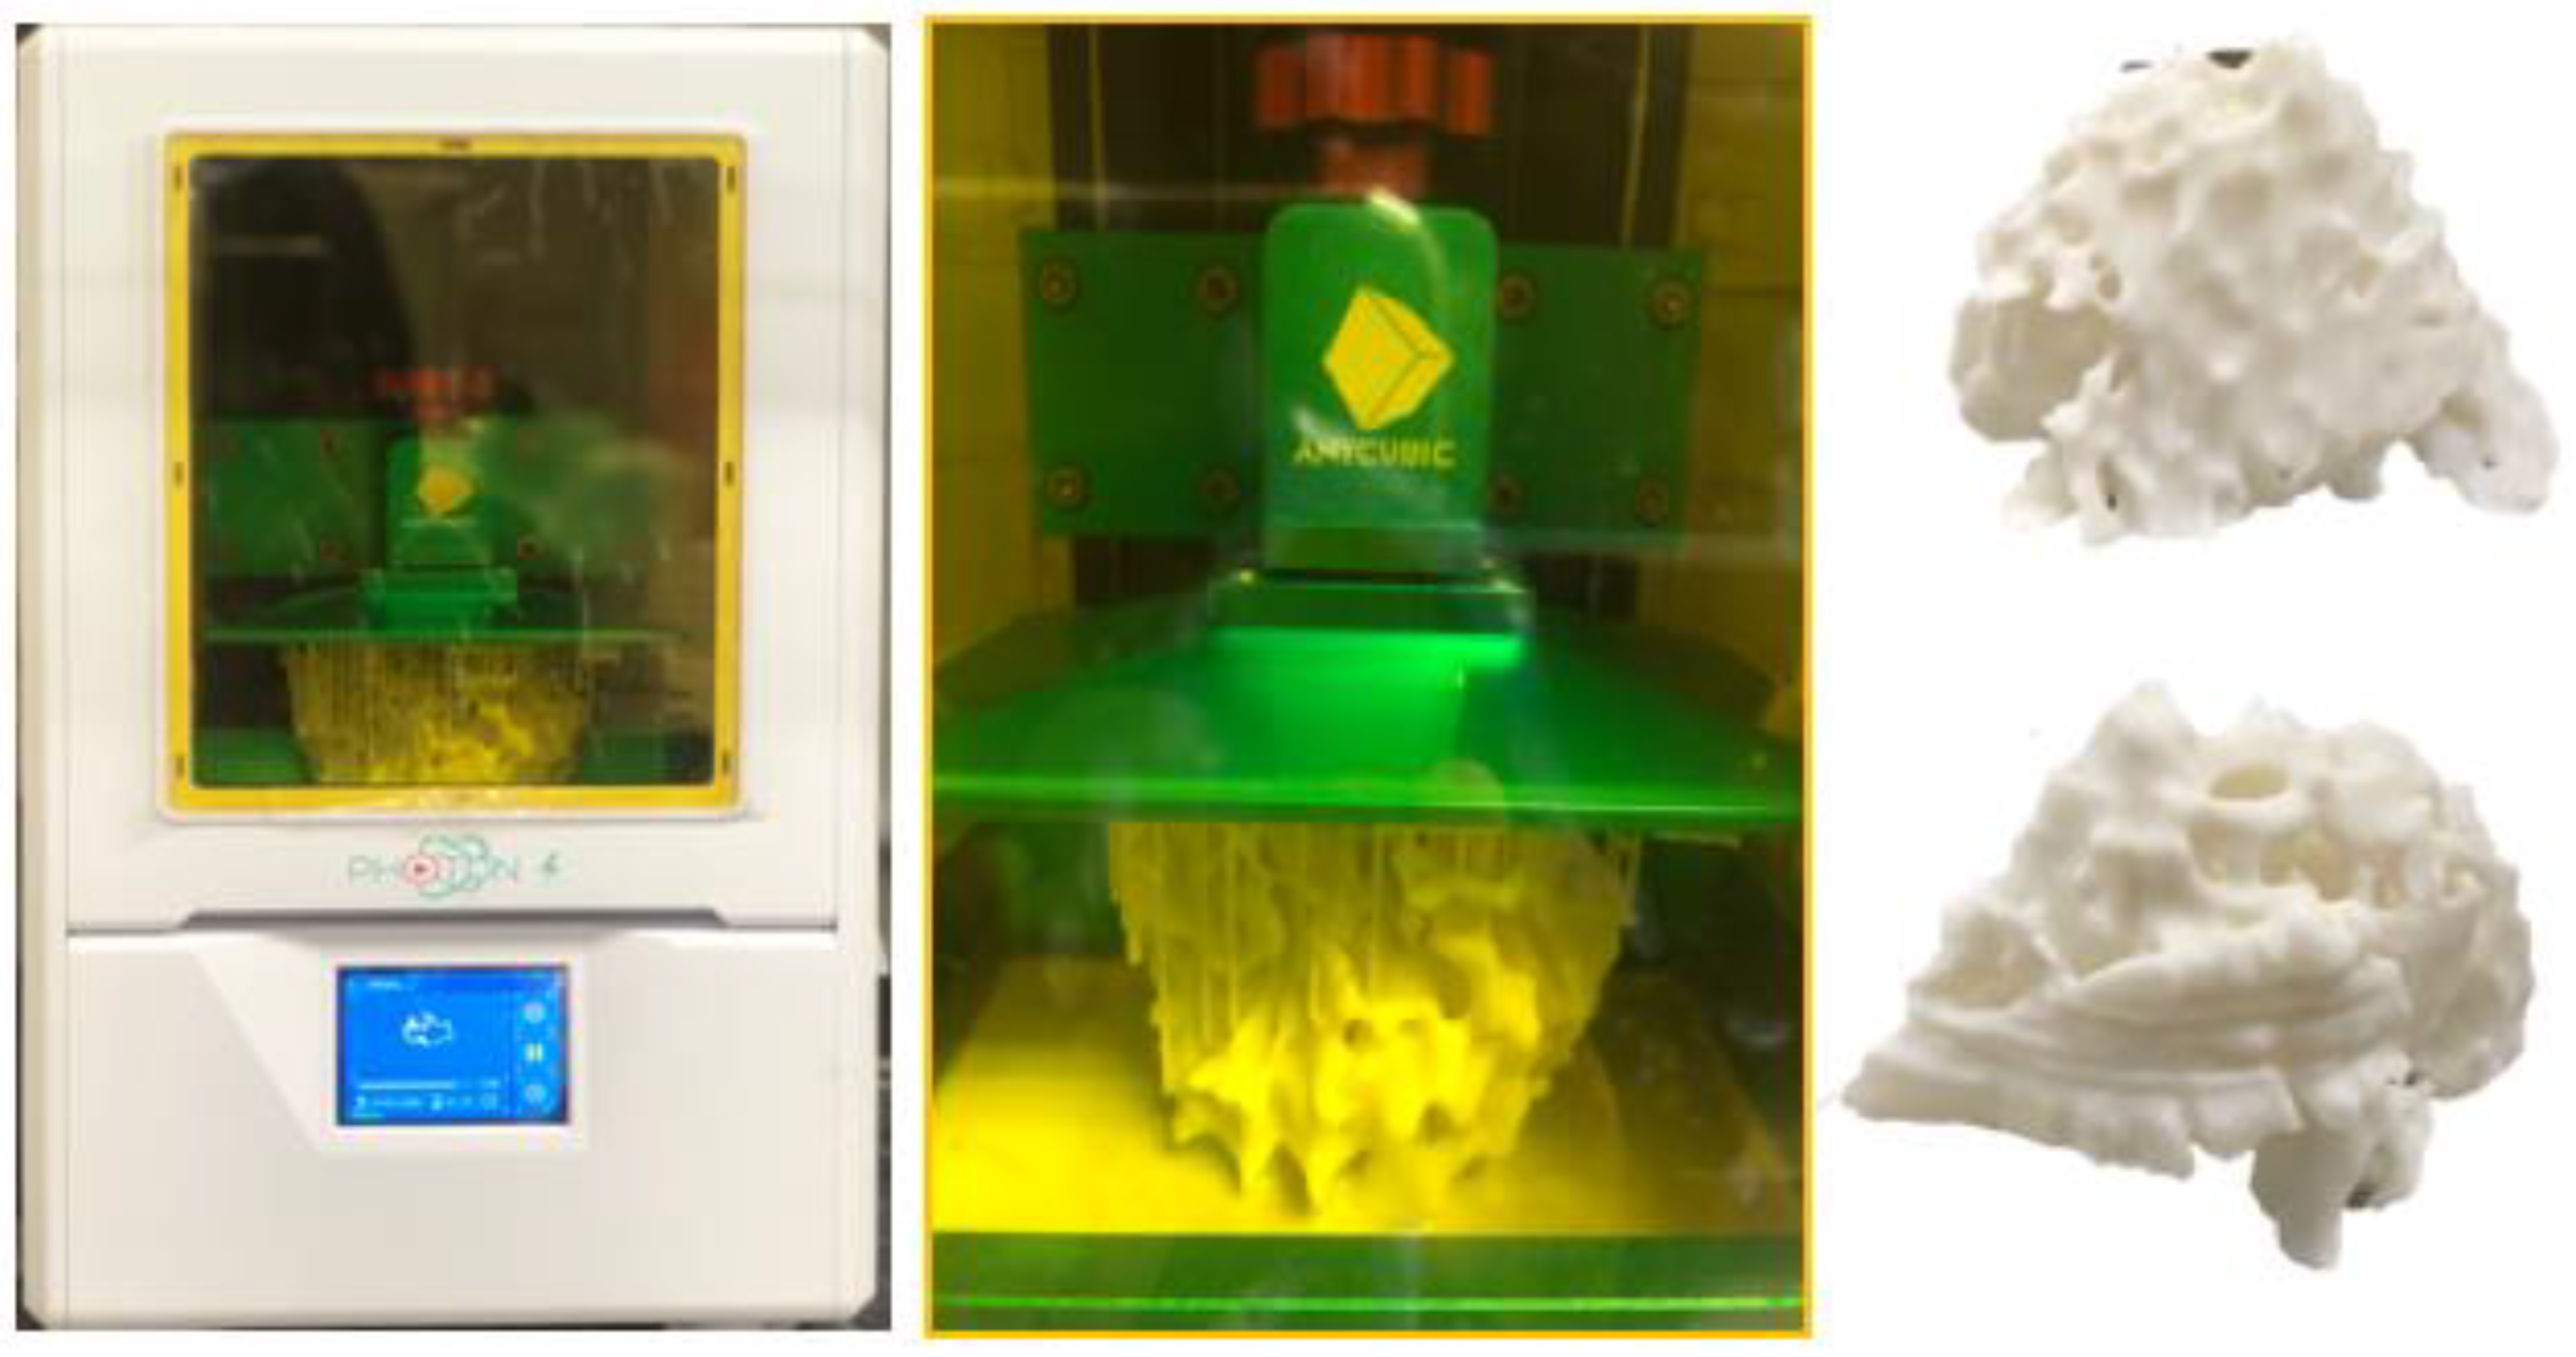

5.1. 3D-Printed Breast Cancer Model

- Sindi, R.; Wong, Y.H.; Yeong, C.H.; Sun, Z. Development of patient-specific 3D-printed breast phantom using silicone and peanut oils for magnetic resonance imaging. Quant. Imaging Med. Surg. 2020, 10, 1237–1248. [Google Scholar] [CrossRef]

- Sindi, R.; Wong, Y.H.; Yeong, C.H.; Sun, Z. Quantitative measurement of breast density using personalized 3D-printed breast model for magnetic resonance imaging. Diagnostics 2020, 10, 793. [Google Scholar] [CrossRef]

- He, Y.; Liu, Y.; Dyer, B.A.; Boone, J.M.; Liu, S.; Chen, T.; Zheng, F.; Zhu, Y.; Sun, Y.; Rong, Y.; et al. 3D printed breast phantom for multi-purpose and multi-modality imaging. Quant. Imaging Med. Surg. 2019, 9, 63–74. [Google Scholar] [CrossRef]

| Breast | 1 | MRI | Breast cancer model for breast MRI protocols | Printer: Breast skin shell was printed using Raise3D N2 Plus; Fibroglandular tissues were printed using Anycubic Photon S Materials: Breast skin shell was printed PLA; Fibroglandular tissues were printed using Magma H LINE Photopolymer Resin Cost: USD 30 for breast skin shell and USD 25 for fibroglandular tissues | Breast skin shell was printed at a resolution of 12.5 μm for the x and y-axis planes; 10 μm for z-axis plane Fibroglandular tissues were printed at a resolution of 47 μm for the x, y and z-axis planes Time: ~40 h for breast skin shell and 50 h for fibroglandular tissues |